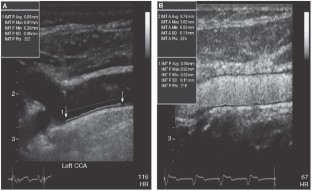

Macioch JE et al. (2004) Effect of contrast enhancement on measurement of carotid artery intimal medial thickness. Vasc Med 9: 7–12

Feinstein SB (2006) Contrast ultrasound imaging of the carotid artery vasa vasorum and atherosclerotic plaque neovascularization. J Am Coll Cardiol 48: 236–243

Shah F et al. (2007) Contrast-enhanced ultrasound imaging of atherosclerotic carotid plaque neovascularization: a new surrogate marker of atherosclerosis? Vasc Med 12: 291–297